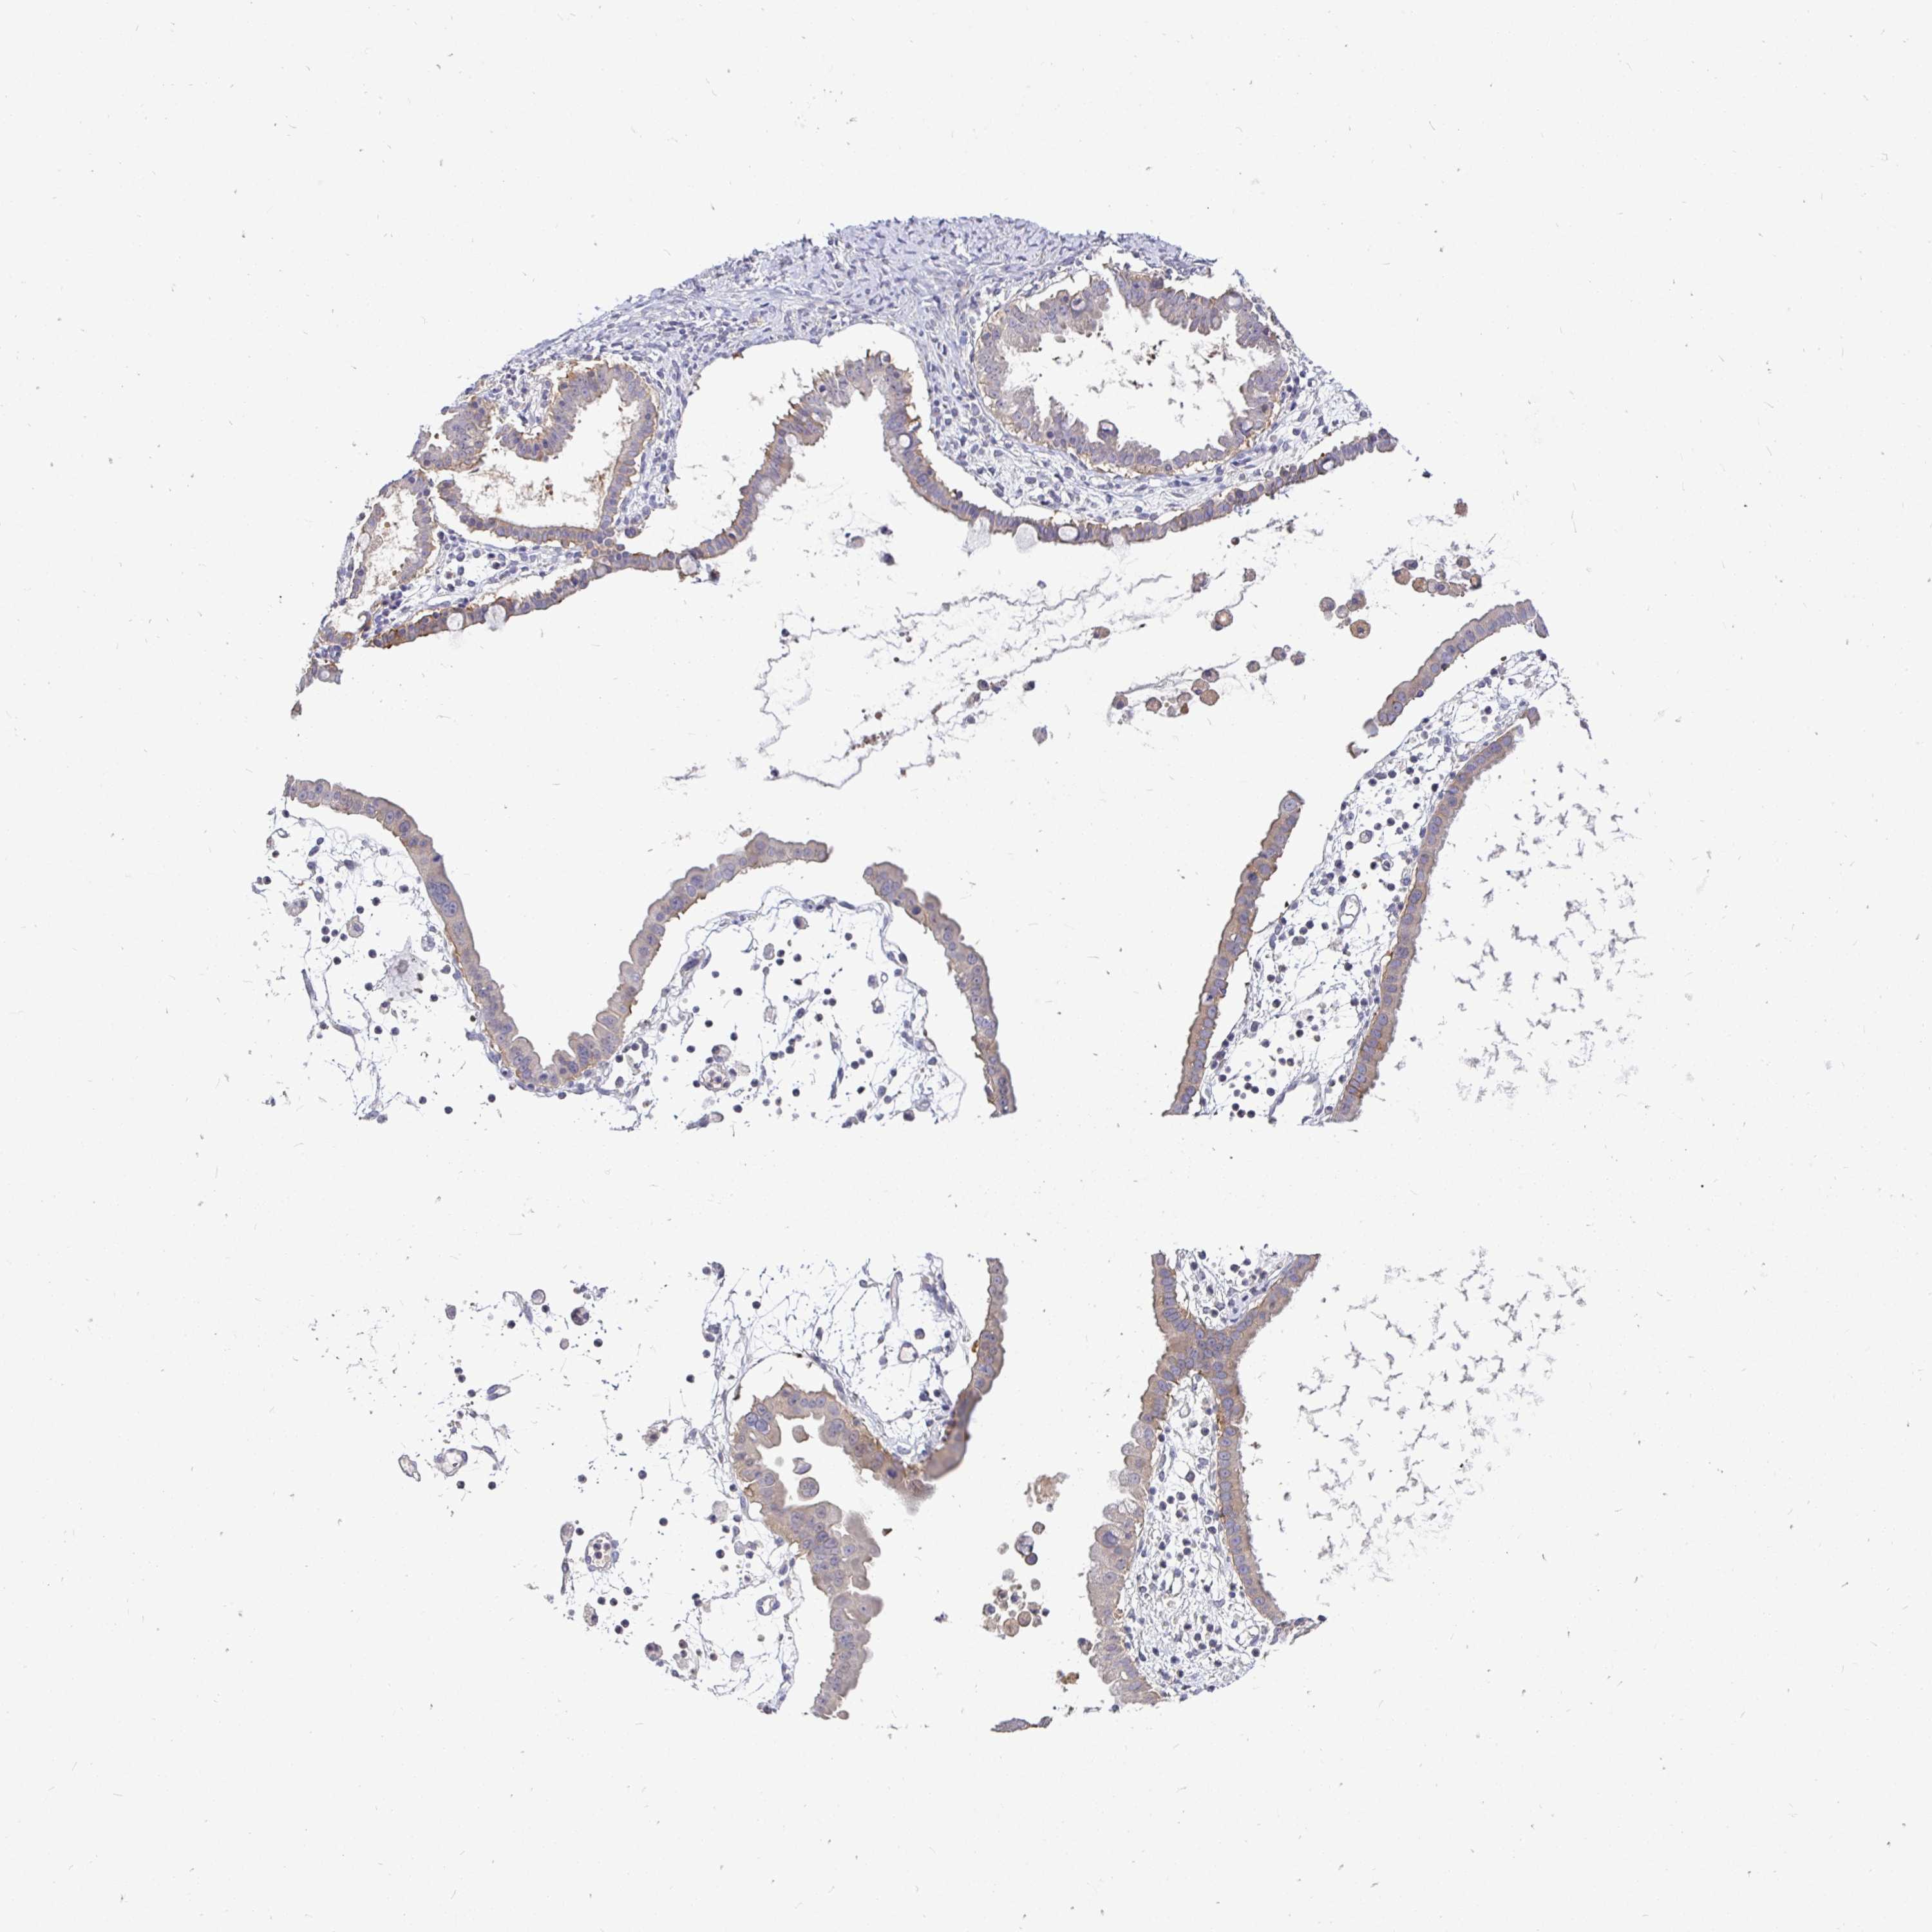

OVARIAN CANCER - Protein expressioni

A mouse-over function shows sample information and annotation data. Click on an image to view it in a full screen mode. Samples can be filtered based on level of antibody staining by selecting one or several of the following categories: high, medium, low and not detected. The assay and annotation is described here.

Note that samples used for immunohistochemistry by the Human Protein Atlas do not correspond to samples in the TCGA dataset.

Antibody stainingi

Antibody staining in the annotated cell types in the current human tissue is reported as not detected, low, medium, or high, based on conventional immunohistochemistry profiling in selected tissues. This score is based on the combination of the staining intensity and fraction of stained cells.

Each image is clickable and will lead to virtual microscopy that enables deeper exploration of all samples and also displays staining intensity scores, fraction scores and subcellular localization as well as patient and tissue information for each sample.

Antibody HPA058432

Antibody CAB022079

Carcinoma, endometroid